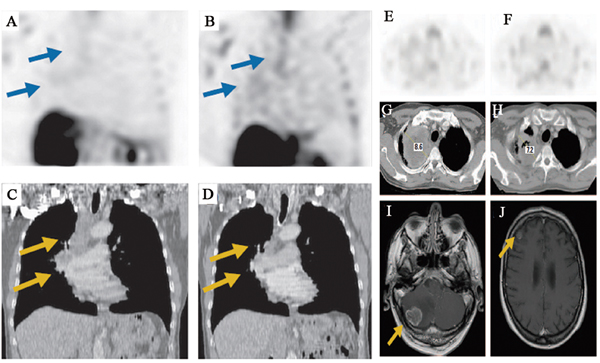

In oncology trials, 99mTc-Annexin V could provide insight into the biology and native apoptosis in tumors. The study in 18 patients with head and neck cancer showed a well correlation between the quantitative 99mTc-Annexin V tumor uptake and the number of apoptotic tumor cells derived from TUNEL assays. However, mean percentage absolute tumor uptake of the injected dose per cm3 tumor volume was only 0.0003 % at 1 hour post-injection and 0.0001 % at 5 to 6 hours (P = 0.012) [23]. In another study in intracardiac tumor patient, it indicated that, as the high apoptotic index is found frequently in malignant but not in benign tumors, 99mTc-Annexin V imaging may be helpful to study tumor biology in a noninvasive way which is difficult to access for biopsies [24]. Overall, these results have demonstrated that 99mTc-Annexin V has the capability for binding to apoptotic tumor cells and the ability to study tumor biology in patients. Other studies have been proposed to evaluate its clinical feasibility for imaging apoptosis following cancer therapy to predict response. 99mTc-Annexin V imaging has been used to image patients with breast cancer, lung cancer, lymphoma, head and neck cancer, leukemia, and soft tissue sarcomas treated with varying types of chemotherapy and/or radiation therapy. The 99mTc-Annexin V uptake was correlated well with either Response Evaluation Criteria In Solid Tumors (RECIST) criteria or with cytological and pathological gold standards. In a study of 38 patients with different tumor types (non-Hodgkin lymphoma (NHL) n = 31; non-small-cell lung carcinoma (NSCLC) n = 4; head and neck squamous cell carcinomas n = 3) treated with various modalities of therapy, 99mTc-Annexin V scintigraphy was acquired before and early after the start of treatment [27]. The changes in 99mTc-Annexin V tumor uptake after therapy were visually and quantitatively calculated and correlated to tumor response according to RECIST criteria. A statistically highly significant correlation was found between changes in 99mTc-Annexin V tumor uptake and clinical response (r2 = 0.62; P < 0.0001). Similarly, in a phase II/III study 99mTc-Annexin V scintigraphy was performed to evaluate the early response of platinum-based chemotherapy before and within 48 hours after the start of therapy in 16 patients with advanced NSCLC. It showed a significant correlation between the 99mTc-Annexin V tumor uptake and treatment outcome (r2 = 0.86; P = 0.0001). As shown in Figure 1, patients with notably increased Annexin V tumor uptake showed complete or partial remission while patients with stable or progressive disease demonstrated less prominently increased or decreased uptake of 99mTc-Annexin V [28]. Collectively, these studies indicate that 99mTc-Annexin V scintigraphy might be valuable as a predictive test for early therapy response during the process of treatment. Table 2 summarizes other clinical trials with 99mTc-Annexin V imaging in oncology. In the field of nuclear medicine, 18F-FDG PET imaging has been considered as the gold standard for evaluation of oncology patients [75]. However, the radiopharmaceutical 18F-FDG could not specifically image apoptosis induced by chemotherapy or radiation therapy. Confounding imaging patterns such as reactive inflammation versus residual tumor may occur in 18F-FDG PET imaging [76]. Nevertheless, imaging of apoptosis with 99mTc-Annexin V, immediately before and after therapy, may complement the deficiency in 18F-FDG PET imaging of malignancies in time [50].

Figure 1: 99mTc-Annexin V SPECT imaging of tumor response during platinum-based chemotherapy in advanced lung cancer. A. Baseline and B. follow-up 99mTc-Annexin V imaging demonstrate chemotherapy-induced increase of tumor tracer uptake (arrows). C. Baseline computed tomography demonstrates solid mass in the right upper lobe enlarged mediastinal lymph nodes (arrows). D. Follow-up computed tomography scan 8 weeks after the start of chemotherapy shows complete response (arrows). E. Baseline and F. follow-up 99mTc-Annexin V imaging demonstrate therapy-induced decrease of Annexin V uptake. G. Baseline computed tomography shows heterogeneous mass in the right upper lobe. Follow-up H. computed tomography and magnetic resonance scans obtained 4 weeks later demonstrate local stable disease and brain metastases (arrows) in the I. cerebellum and J. right frontoparietal area.